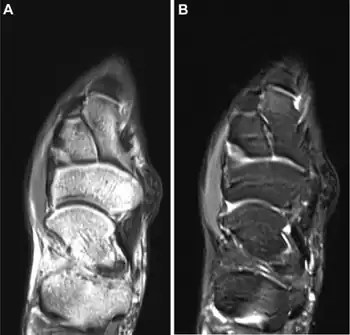

| a,b)MRI appearance of surfers' knot medial to the persons' navicular | |

Surfer's knots are a cutaneous condition caused by chronic pressure over bony prominences leading to thick fibrotic nodules on knees, knuckles, dorsal feet, often seen with those who perform surfing, boxing, football, and marbles.[1]